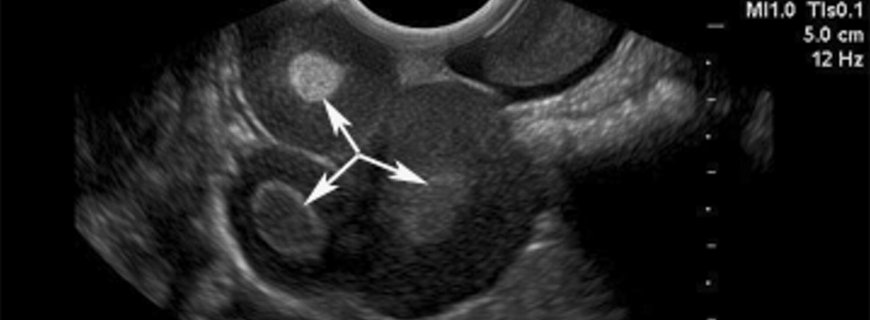

İyi huylu kistik teratom yumurtalığın germ hücrelerinden gelişen yavaş büyüyen bir tümördür. Teratomun boyutları birkaç milimetreden 25 cm çapa kadar değişebilir. Çoğu teratom 10 cm\'den küçüktür ve tek taraflı gelişir. Hastaların %10 ila 15\'inde iki taraflıdır. Muayenede bu tümörler hamur kıvamındadır. Kistin duvarları düzgün yüzeyli, parlak ve opak beyaz renklidir. Açıldıklarında kistin içinden genellikle büyük saç kütleleri ve kıkırdak ve diş alanları bulunan kalın yağlı bir sıvı boşalır. Deri ve deri ekleri (yağ bezleri, ter bezleri, saç follikülleri, kas fiberleri, kıkırdak, kemik, diş, sinir hücreleri ve solunum ve sindirim sistemi yollarının epiteli gibi) görülebilir.

Yarısından çoğu belirti vermezler ve rutin muayene sırasında saptanabilir, karın grafisi ya da ultrasonografide tesadüfen görülebilir ya da başka nedenle yapılan bir ameliyatta tesadüfen bulunabilir. Kistik teratomlar muayene sırasında tesadüfen kite olarak saptanır.